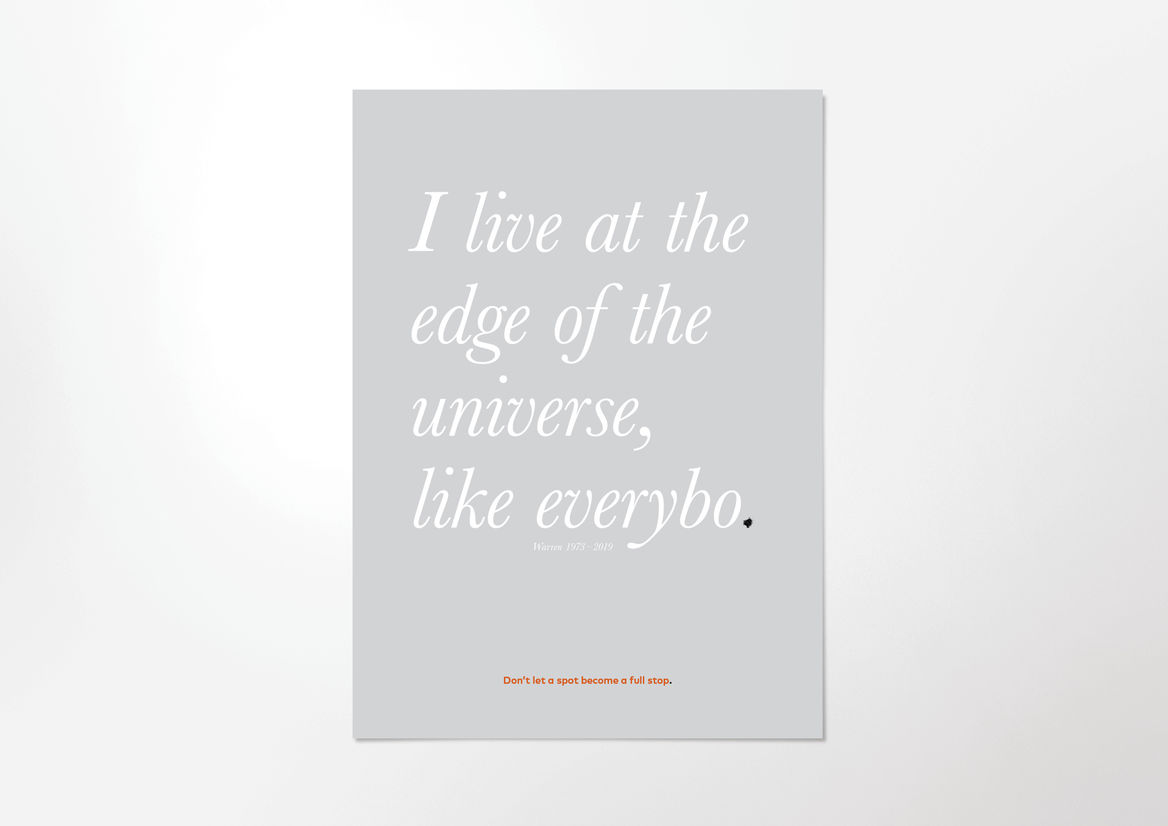

The Melanoma Typeface is a font that taught an entire nation to take a second look at their spots.

We created a usable font, made up of seven glyphs of a single character - the full stop. Each glyph was designed in partnership with New Zealand medical professionals to accurately represent one of the visual symptoms of Melanoma. When viewed at a small size, the glyphs all look like slightly misshapen full stops. But as point size increased, more and more detail is revealed in each character, until the true nature of each spot is impossible to ignore.

These seven simple characters could turn any piece of design or messaging into a melanoma awareness campaign, simply by swapping out their full stop for ours.

Our Melanoma Typeface transformed regular communications into an educational piece, showing the public that a cancerous spot can hide in plain sight.